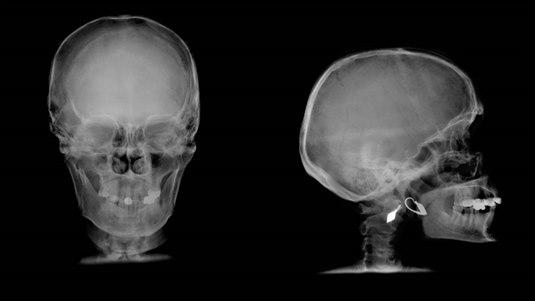

Du er nå blitt undersøkt og/eller innlagt til observasjon i sykehus for en hodeskade med mulig hjernerystelse. Det er ikke funnet tegn på at hodeskaden har vært alvorlig, og det anses derfor trygt å sende deg hjem. Dette er en informasjon om noen problemer som kan dukke opp etter utskrivingen.